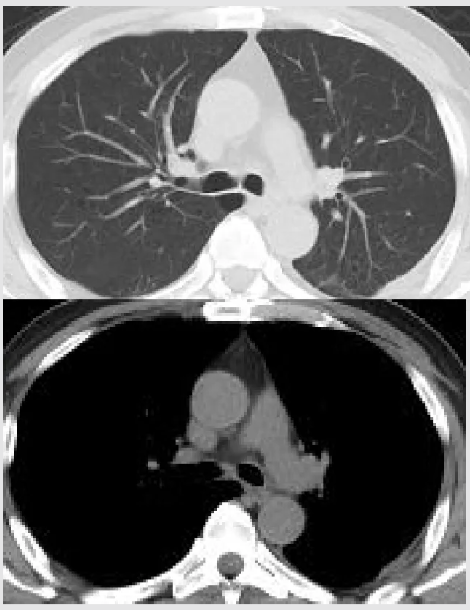

2026-01-05 随访WBC 4.72×10^9/L,N 66.4%;hsCRP 5.8mg/L,ESR 66mm/h,PCT 0.38ng/mL;ALT/AST 91/69U/L,D二聚体 1.01mg/L;炎症降至正常。胸部平扫CT:左侧胸腔积液较前25-12-24减少;两肺上叶新增炎症,治疗后随访;左下肺渗出、部分不张,较前稍好转,纵隔小/稍大淋巴结(较前变小)。

2026-01-20 出院后体温平,无咳嗽咳痰,胸腔引流管无引流液;WBC 7.13×10^9/L,N 63.0%;hsCRP 0.6mg/L,ESR 13mm/h,PCT 0.08ng/mL;ALT/AST 28/33U/L,D二聚体 1.09mg/L;炎症标志物均降至正常,胸部平扫CT:左侧胸腔积液较前26-01-05减少;两肺上叶炎症,较前好转;左下肺渗出、部分不张,较前好转,纵隔小/稍大淋巴结(较前相仿)。予拔出胸腔引流管。嘱继续阿莫西林克拉维酸0.457g bid+甲硝唑0.4g tid口服,2周后感染病科门诊随访。